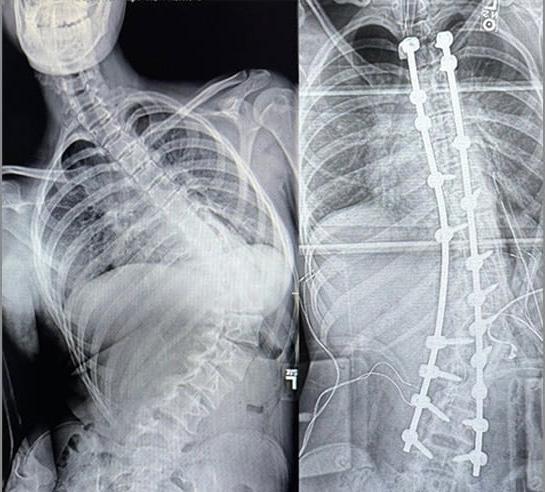

Dr. David Siambanes, a BayCare Medical Group pediatric orthopedic surgeon, specializes in spinal procedures at St. Joseph’s Children’s Hospital. One of his patients, 17-year-old Madison Lockert, was born with hypotonic cerebral palsy and developed severe scoliosis as a teen, which curved her spine to a painful 98-degree angle that limited her ability to walk.

Following an eight-hour spinal fusion surgery by Dr.

Siambanes and his team, Madison gained the ability to stand tall. “She’s so much happier,” said her mother, Grace Lockert. “Her quality of life is so much better, and she can now even walk longer distances. It’s just incredible what Dr. Siambanes and his team were able to achieve.”